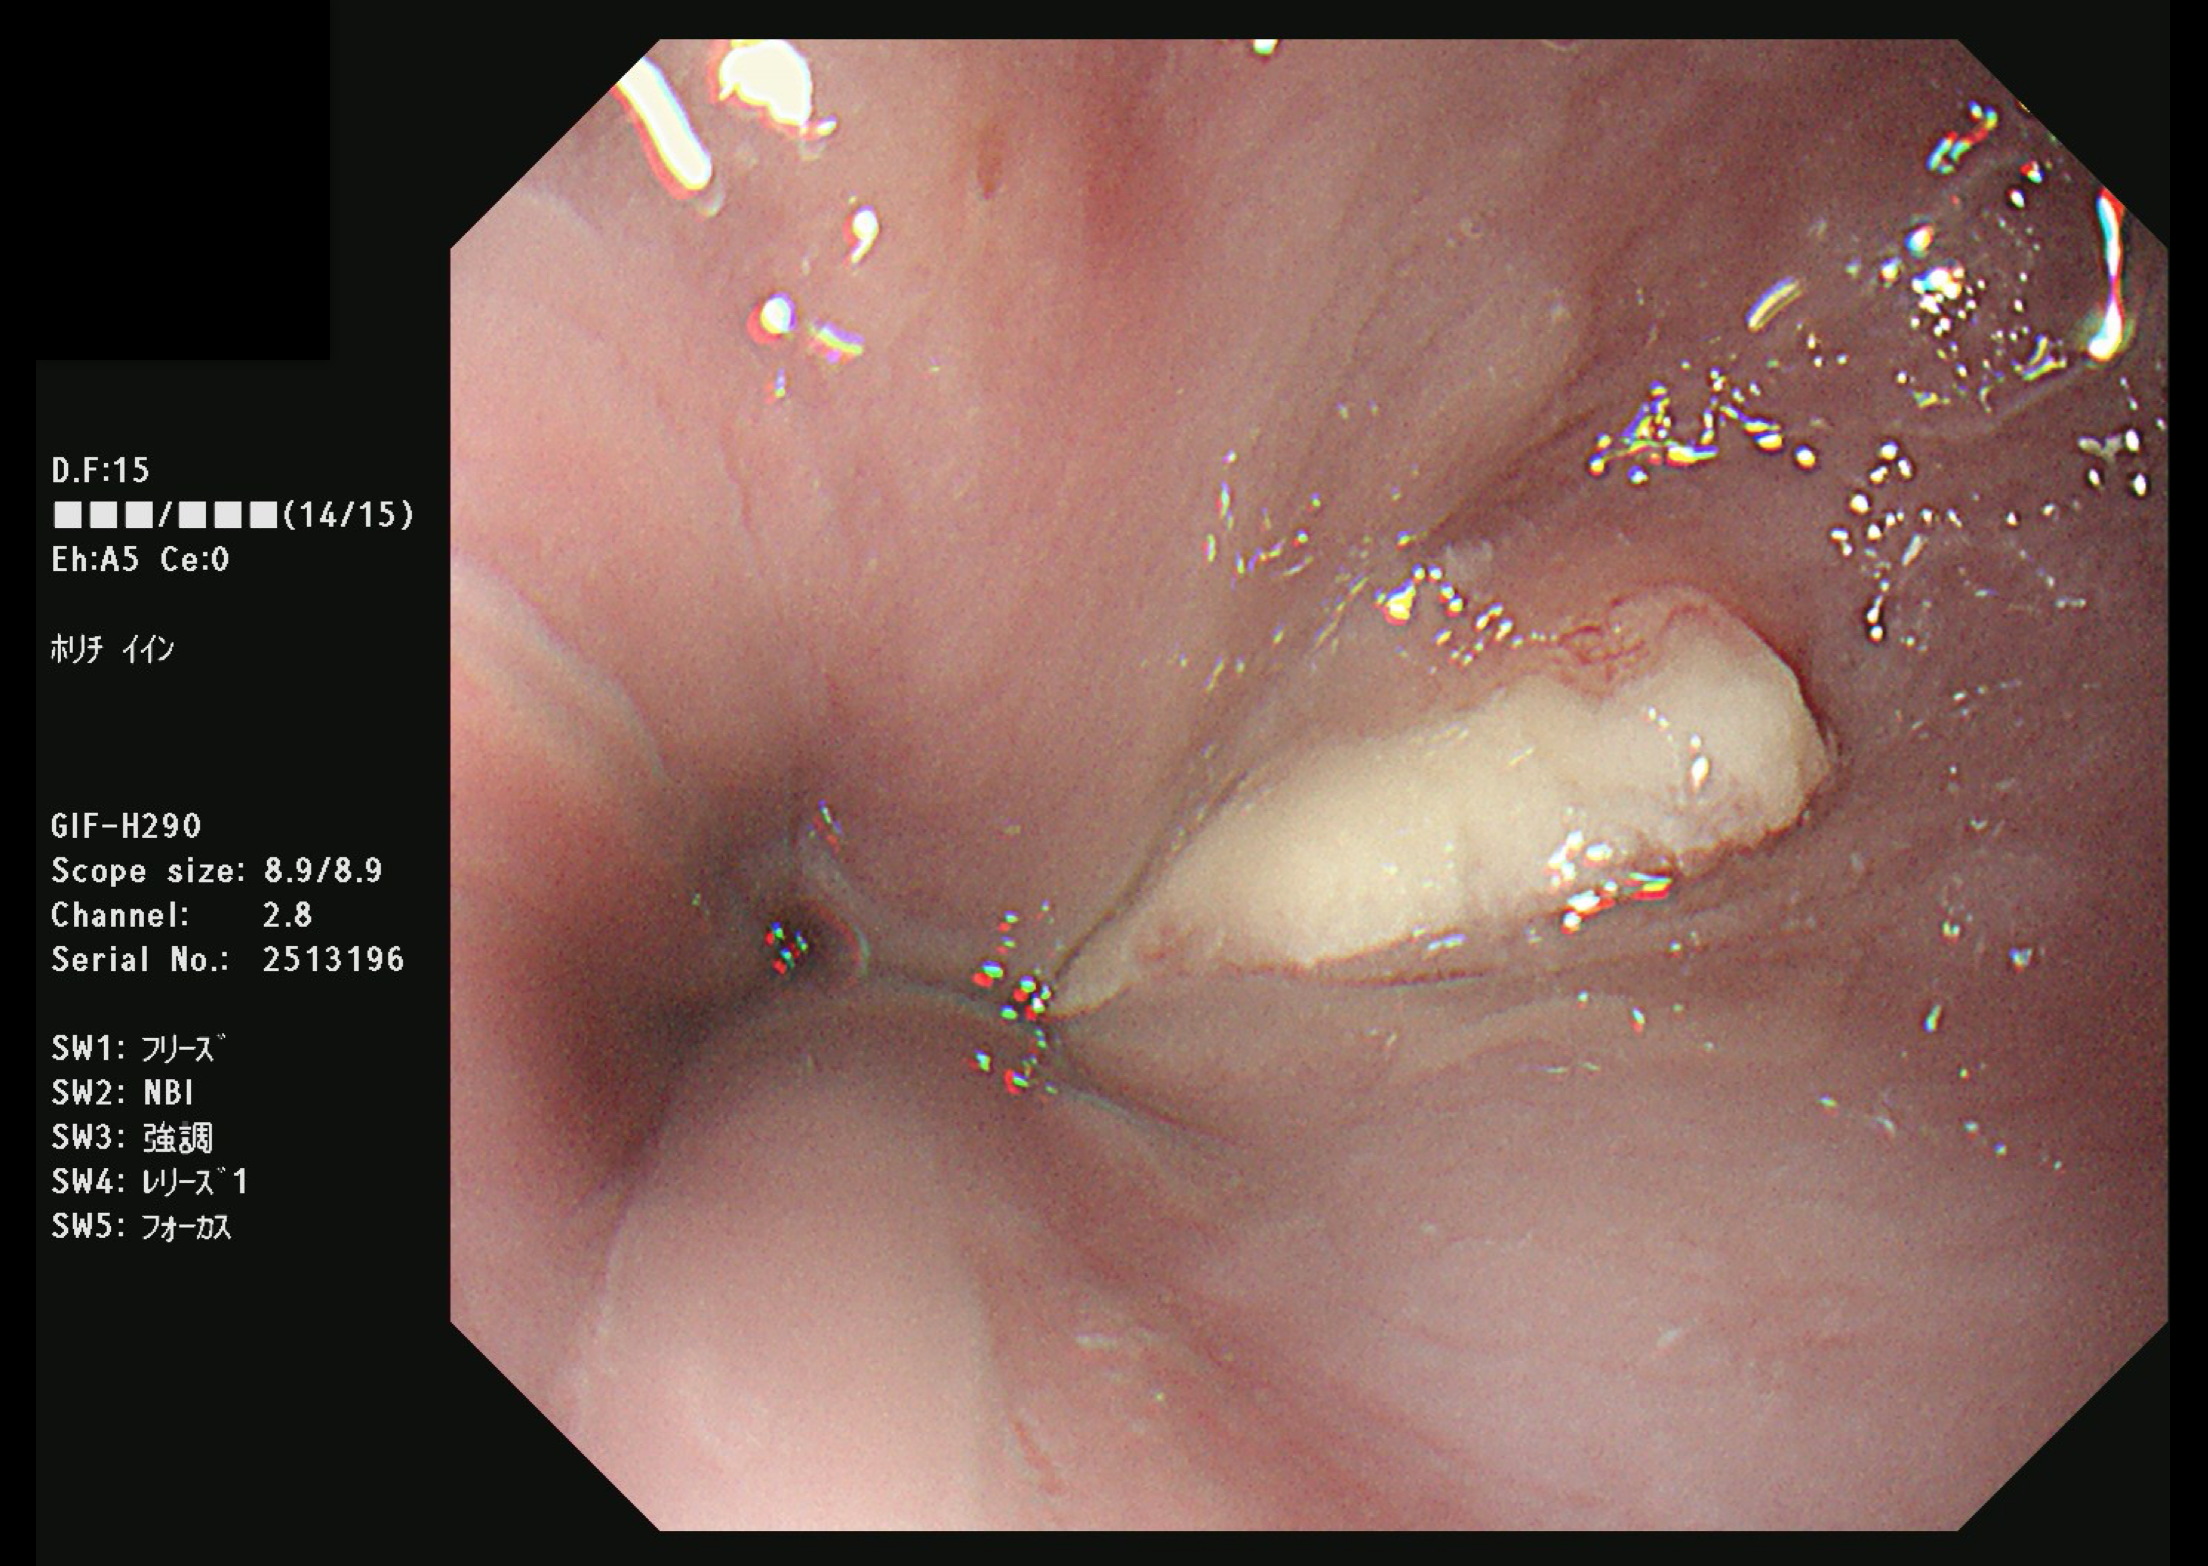

胃がん(上部消化管内視鏡)

食道がん(上部消化管内視鏡)

胃がん検診

富山市の胃がん検診は胃内視鏡(上部消化管内視鏡)もしくは胃透視(バリウムを飲む検査)でおこなわれています。胃がんはかつては日本人にとって非常に多いがんでしたが、ヘリコバクターの保菌者の減少とともに、胃がんも少なくなりつつあります。

胃がん検診では喉頭部・食道・十二指腸上部を観察します。

当院では胃内視鏡(経口)のみを実施しております。胃の中を十分に検査するために高解像度の内視鏡を使用しており、そのため口からの内視鏡検査となります。一般的に鼻からの経鼻内視鏡による検査の方が楽な検査と言われていますが、内視鏡が細い分、最新型の経口高解像度内視鏡に比べて解像度が落ちます。

富山市からの検診の案内には経鼻内視鏡のできる施設が明示されていますので、ご希望に合わせて受診してください。